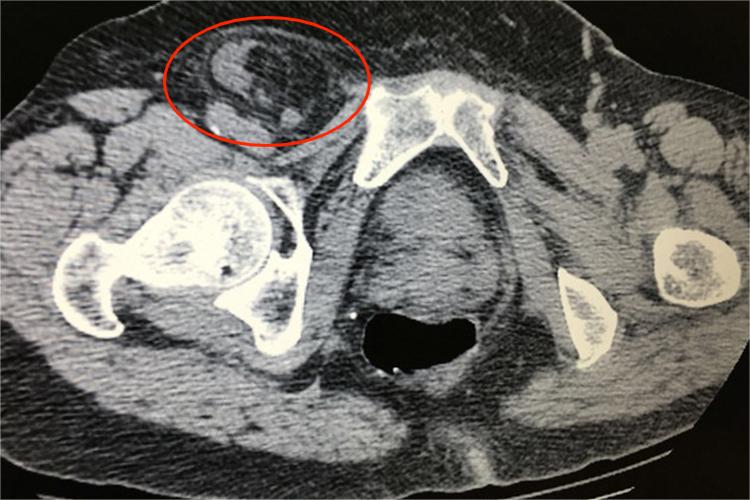

疝的诊断可依据病史、症状和体格检查明确。最重要的还是在临床检查的基础上选择合理的辅助检查,常用的可辅以超声、MRI/CT等影像学检查。